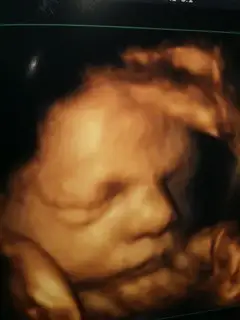

Benim bebeğim 32.haftasına kadar hep 2 hafta önde gidiyordu bugün baktı doktor kilosu 2400müş eğer ben böle kilo almaya devam edersem 3 ila 3200 arası doğarmış hatta 2900 bile olabilirmiş ama dikkat edersem 3600 geçermiş 30.haftada bana 4e yaklaşaır demişti bu son bir ay hayatımdan ekmeği karbonhidratlı herşeyi çıkarcam herşey kızım için.. Kilosu çokda önemli değil sağlıklı gelsin de.. Bir de doktor böbreklerinde genişleme var dedinormalde 2cm olması gerekirsen bebğimin 6cm miş 10 cm e kadar bişey olmazmış ama doğumdada böle olursa gözlem altında tutacaz dedi Onun dışında herşey çok iyi boyu uzunmuş anası gibi :) Yüzünü net bi şekilde gördüm elmacık kemikli olacak sanırsam yerim onu.. Rabbim tüm annenlere ve bebeklerine sağlık sıhhat hayırlı doğumlar nasip eylesin...

Benim bıdık hiç yüzünü göstermedii yaaaa hep saklıyor bıdık gelsin dünyaya bak ben yüzünü nasıl seyrediyorum hım saklasın bakalım saklayaiblirse:)).

herşeyimiz yolunda çok şükür kayram 2500 gr 45 cm olmuşşmaş deyin kızlar hergün okuyorum onu nazar olcak diye normal doğum pozisyonunu almış yavrum ama sanırım sezryan olcak çünkü iri olcak dedi doktor başı da öndeymiş biraz normal doğum olamayabilir dedi oysaki çok istiyodum ama napalım oğluşum iyi olsun da .. iki hafta sonra 35 olcaz o zaman aşağı yukarı belli olur dedi.. nst ye de almadı 35 ten önce gerek görmüyorum dedi.. çok güzel de pozlar verdi kuzum bize çok net görünüyodu bi ara dilini falan çıkarıyodu belki de o an su yutuyodu :) ama çok tatlıydı yaa yerim kuzumu ben